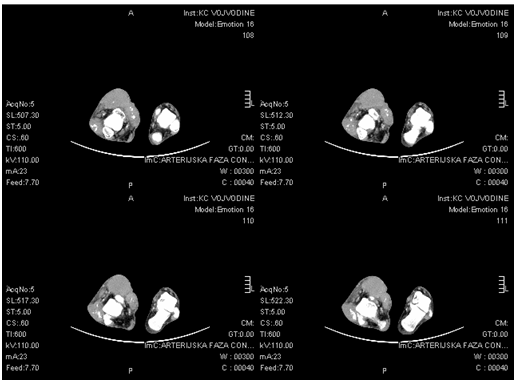

Wound was immediately irrigated and debrided. Cottons swabs were taken for bacteriological. Full laboratory analysis and knee and ankle joint X rays were taken. The results show the existence of a local infection caused by Staphylococcus aureus, but without bone involvement. Antibiotics were given and computerized tomography (CT) and magnetic resonance (MRI) was performed. CT and MRI uncovered the presence of fusiform expansive multicentric changes in the region of thigh, knee and lower leg (Figure 4) approximate dimensions 26 x 10 x 22cm (CC x x LL AP) and in the region of the ankle joint (Figure 5) 16 x 5cm (AP x LL). Tumor changes had characteristics of desmoid tumor, which was confirmed by repeated histological analysis (Figure 6). Limb salvage procedure was done, tumefaction in the right knee and ankle were partial surgically removed. Because tumor had multicentric localization with osseous involvement, any attempt of complete removal of the tumor led to the amputation of the leg. During operation, full passive range of motion of the knee and ankle joint were confirmed. Big resection of soft tissue resulted in large skin defect, which was without any possibility of primary closure. Wound was closed using local skin grafts in cooperation with plastic surgeons. Postoperative adjuvant hormone and anti-inflammatory therapy, recommended by oncologist (Tamoxifen 120mg and Sulindac with doses of 3mg/kg daily, one year postoperatively), was immediately started. Follow up controls were uneventful, wound healed completely. Two years later patient had full knee and ankle range of motion without any new tumor growth (Figure 7).

Figure 5 Axial CT presences of right ankle joint tumor infiltration.